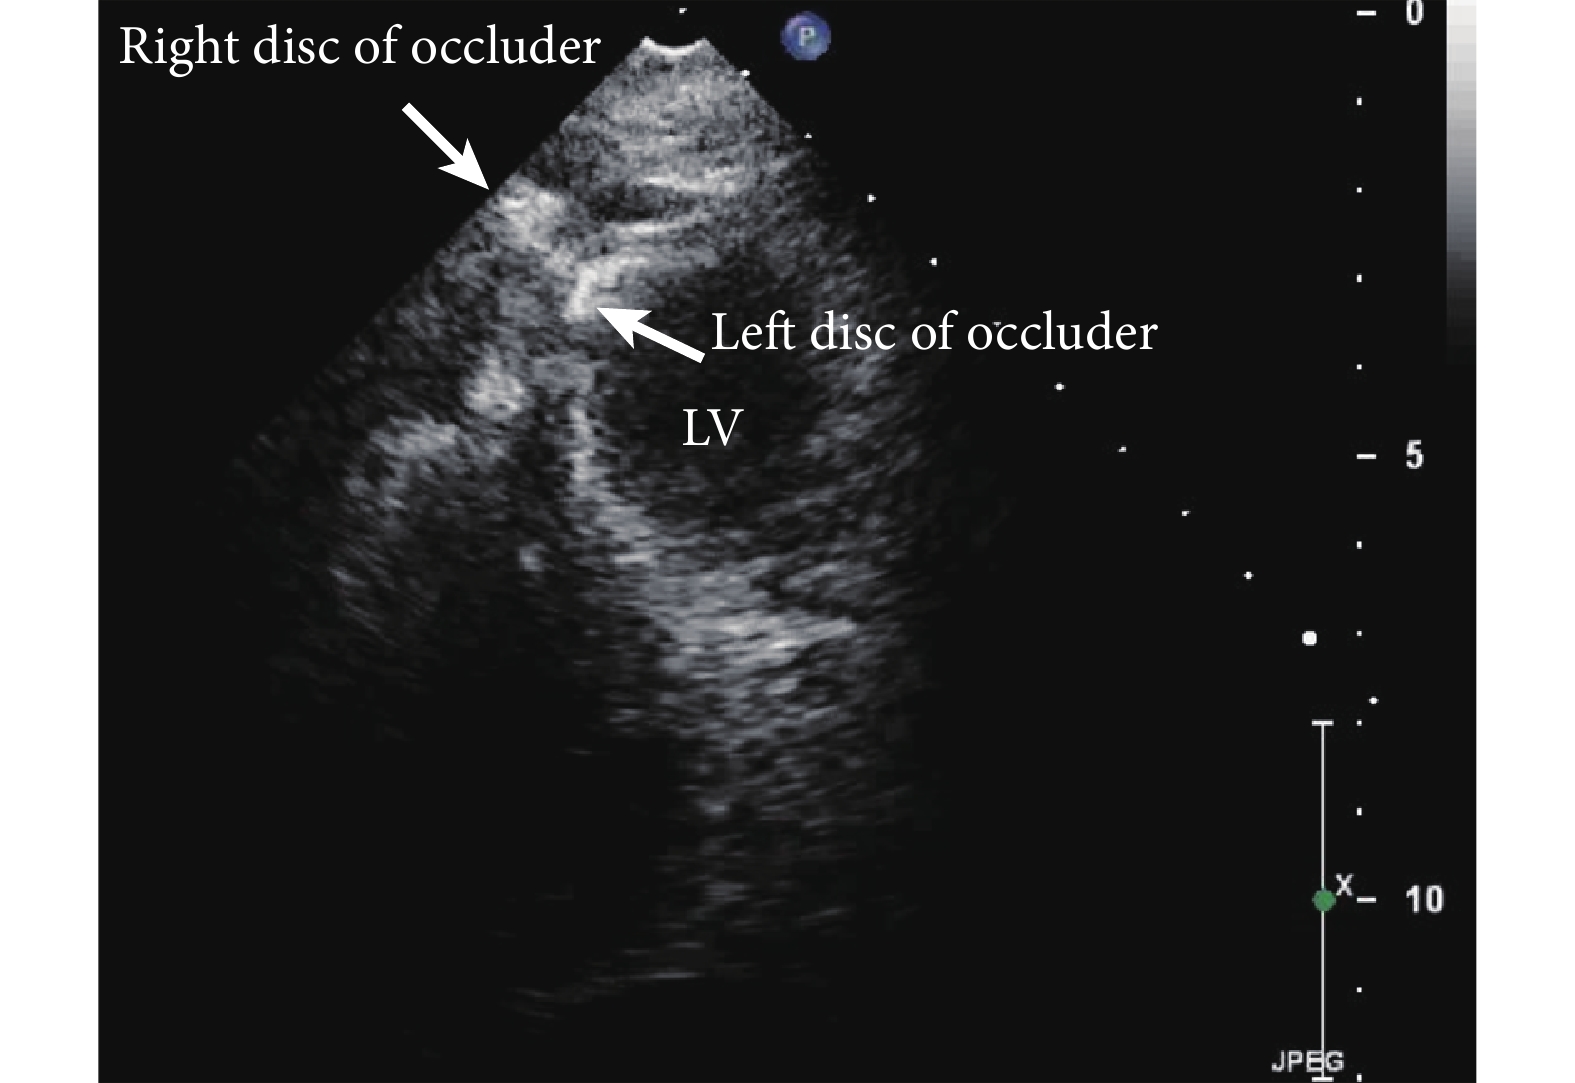

將前述虛擬空間連線分別在 CT 的冠狀面、矢狀面和橫斷面上進行投影,并建立平面坐標。將位于患者冠狀面上且垂直于患者長軸的虛擬軸線定義為 X 軸,將同一平面上平行于患者身體長軸的軸線定義為 Y 軸,垂直于冠狀面的軸線定義為 Z 軸。分別測量冠狀面連線投影與 X 軸夾角(∠1)、矢狀面投影與 Y 軸夾角(∠2)、橫斷面投影與 X 軸夾角(∠3)(圖 3)。術中以體表穿刺點為原點,在上述 XYZ 軸確定的虛擬空間內操作,將穿刺針針尖置于體表穿刺點,預估針體在各投影平面上與軸線的三個夾角∠1′、∠2′、∠3′。確定角度后,囑麻醉醫師暫時斷開呼吸機管路,使肺組織塌陷回縮,迅速完成穿刺。見到鮮紅色回血后,再結合術中 TEE/3D-TEE 的實時監測確認穿刺針進入左心室心腔(圖 4)。經穿刺鞘管針導入引導鋼絲,再交換穿刺鞘管即可完成經皮穿刺左心室通道的建立。通常情況下,遵循上述步驟完成的穿刺由于已經基本固定了由心尖到達目標的方向,故可以很好地建立由穿刺點到病灶處的軌道,后期 TEE 也能較好地完成引導,而無需大幅度的調整。

LV:左心室